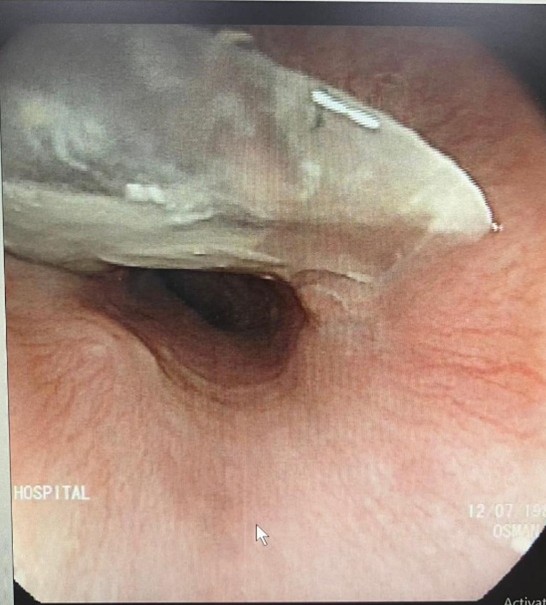

The patient was immediately evaluated by our Gastroenterology team. An urgent upper endoscopy (EGD) was performed, which revealed the fish bone firmly impacted in the upper esophagus. Using biopsy forceps, the bone was carefully extracted. A follow-up inspection showed an area of erosion where the bone had been embedded, but thankfully, no further complications were noted.